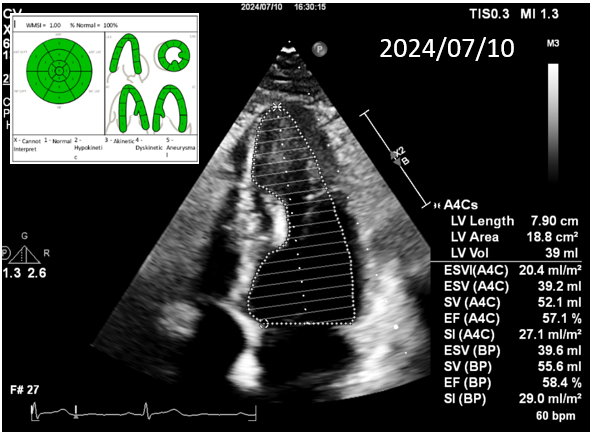

During the staged PCI, antegrade approach with escalating guidewires ended up in subintimal space; retrograde approach from the first LAD-septal branch failed because there was difficulty crossing the existing mid-LAD stent. Further attempts from the third septal branch successfully reached the distal cap of the CTO via proximal descending artery, finally entering the antegrade guide extension catheter by rendezvous technique. After wire externalization and POBA for RCA, the patient became agitated from acute angina, diaphoresis and hypotension. Angiogram of LAD found an acute de novo LAD lesion adjacent to the distal stent edge, leaving only TIMI-1 flow. We stopped the RCA procedure and wired LAD, performed POBA at the de novo LAD lesion and restored coronary blood flow. Then we continued PCI of RCA with POBA followed by the deployment of two DES. Final angiogram showed adequate stent expansion and TIMI-3 flow in RCA. The patient was discharged with no further complications. Follow-up echocardiogram three months later showed improved wall motion and ejection fraction, indicating good myocardial recovery.